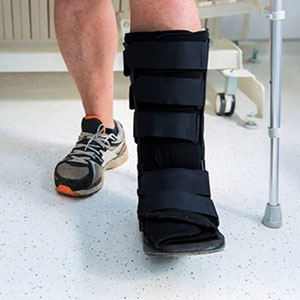

- Get back on your feet quickly in a walking boot

- Get back on your feet quickly in a boot; many cases within 2 weeks

Walk in a boot and return to daily activities